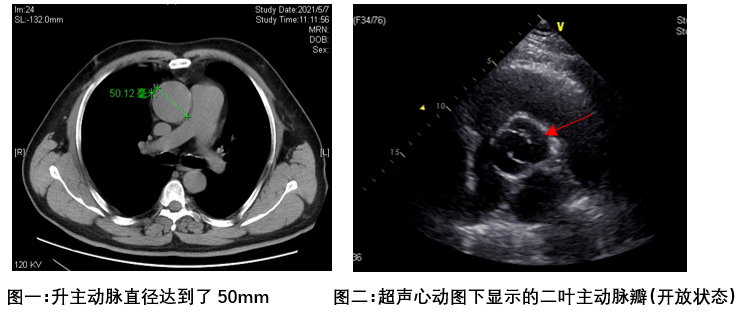

显然吴先生恰恰就是这1/200概率中的一员。就目前的指南及专家共识来说,主动脉瓣二叶瓣化畸形 主动脉瓣返流,合并升主动脉50mm,已经达到了手术治疗的指征,如果不及时治疗,升主动脉继续瘤样扩张,可能会有主动脉夹层甚至破裂的风险。而治疗此疾病最好的手段,便是更换损坏的主动脉瓣膜,同时替换扩张的升主动脉。手术难度系数高,风险较大,当地医院无法进行,所以吴先生慕名来到了北京清华长庚医院。

清华长庚医院心脏外科大血管组负责人崔晓征医师主导评估了他的病情。针对此类疾病,临床上有多种手术方式,评估何种方式最佳需根据每个患者的具体病情敲定。根据CT下升主动脉测量数据达到了50mm,主动脉瓣超声下确实是二叶瓣化畸形,冠脉造影评估回报吴先生并未合并冠状动脉狭窄,崔晓征医师为吴先生选择了主动脉瓣机械瓣置换+升主动脉人工血管置换术(又称为“Wheat’s手术”),最大限度地保证了吴先生冠状动脉血供不受影响,同时缩短了手术时间,提高了手术安全性。目前吴先生术后恢复良好,已顺利出院。